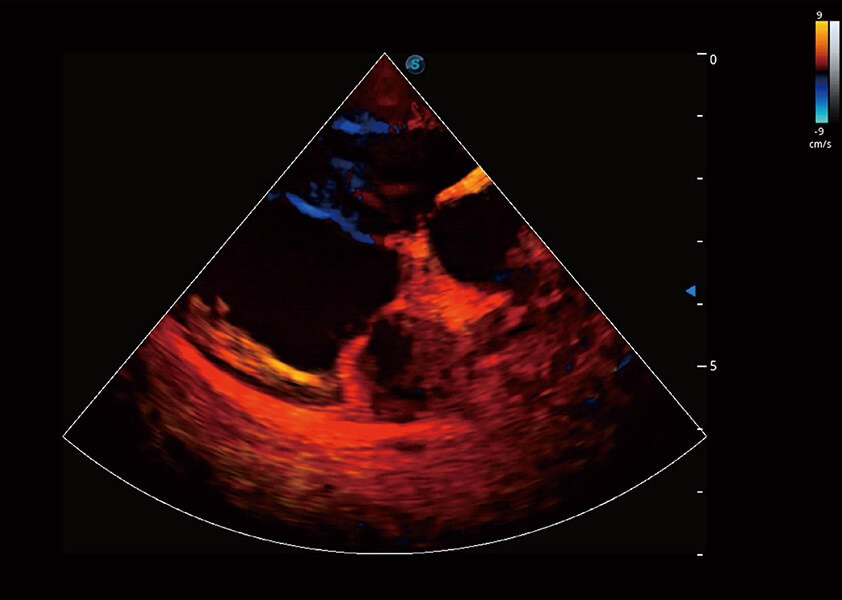

心脏解决方案

ProPet 60 配备了丰富的心脏探头群、先进的成像技术和专业的心脏测量工具,可帮助动物医生为不同体型和生理结构的动物提供心脏和心肌功能的全面评估。

• TDI 组织多普勒成像

实时用颜色表示心肌组织运动,观察和定量组织的运动情况,对快速检测与评估心肌的灌注和活性、电传导及心肌收缩和舒张功能等均能提供重要的诊断信息。

(犬)四腔心血流